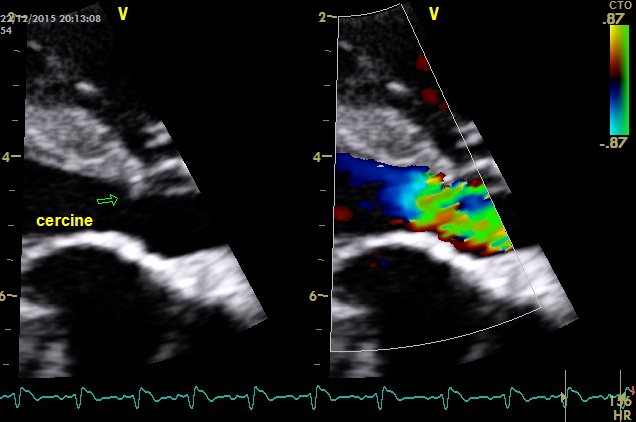

come si puo’ notare dai particolari nelle immagini zoom la struttura valvolare appare integra con una normale conformazione delle cuspidi la turbolenza e’ generata da una piccola banda fibrosa sottovalvolare ,in questo caso a dispetto delle alterazioni minime visualizzabili nell’esame B mode la stenosi sulla base del gradiente appare severa ,il PHT inferiore ai 300mm/sec dell’insufficienza aortica che quasi sempre accompagna la stenosi indica pressioni diastoliche nel ventricolo sx elevate

– Classe 3: la proliferazione endocardica sottovalvolare forma un restringimento di tutto il tratto di efflusso in senso circonferenziale e per tutta la sua lunghezza. Questa lesione, in ecocardiografia, viene classificata come stenosi subaortica a tipo tunnel (tipo 3).Seguendo la classificazione di Pyle la morfologia di questo caso non appare inquadrabile del tutto in quanto non si visualizzano noduli e neanche un ispessimento fibroso che riveste “quasi del tutto” il tratto di efflusso ,il cercine appare limitato al tratto prevalvolare .Bisogna considerare che la stenosi sub-aortica e aortica sono propagate nelle razze e nelle famiglie con base genetica; tuttavia non si conoscono completamente le modalità di trasmissione. Possiamo dire che non è propriamente una malattia congenita perché le lesioni possono non essere presenti alla nascita o, in qualunque caso, non completamente sviluppate. Per questo motivo, una stadiazione clinica non deve essere effettuata prima degli 8-12 mesi di età.